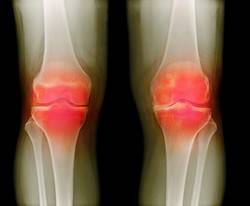

- Рентгенографическое исследование сустава.

- Рентгеновские снимки в нескольких проекциях;

На рентгеновском снимке обнаруживаются дефекты костей колена результат тяжелого течения заболевания.

- рентгенологический метод обследования коленного сустава;